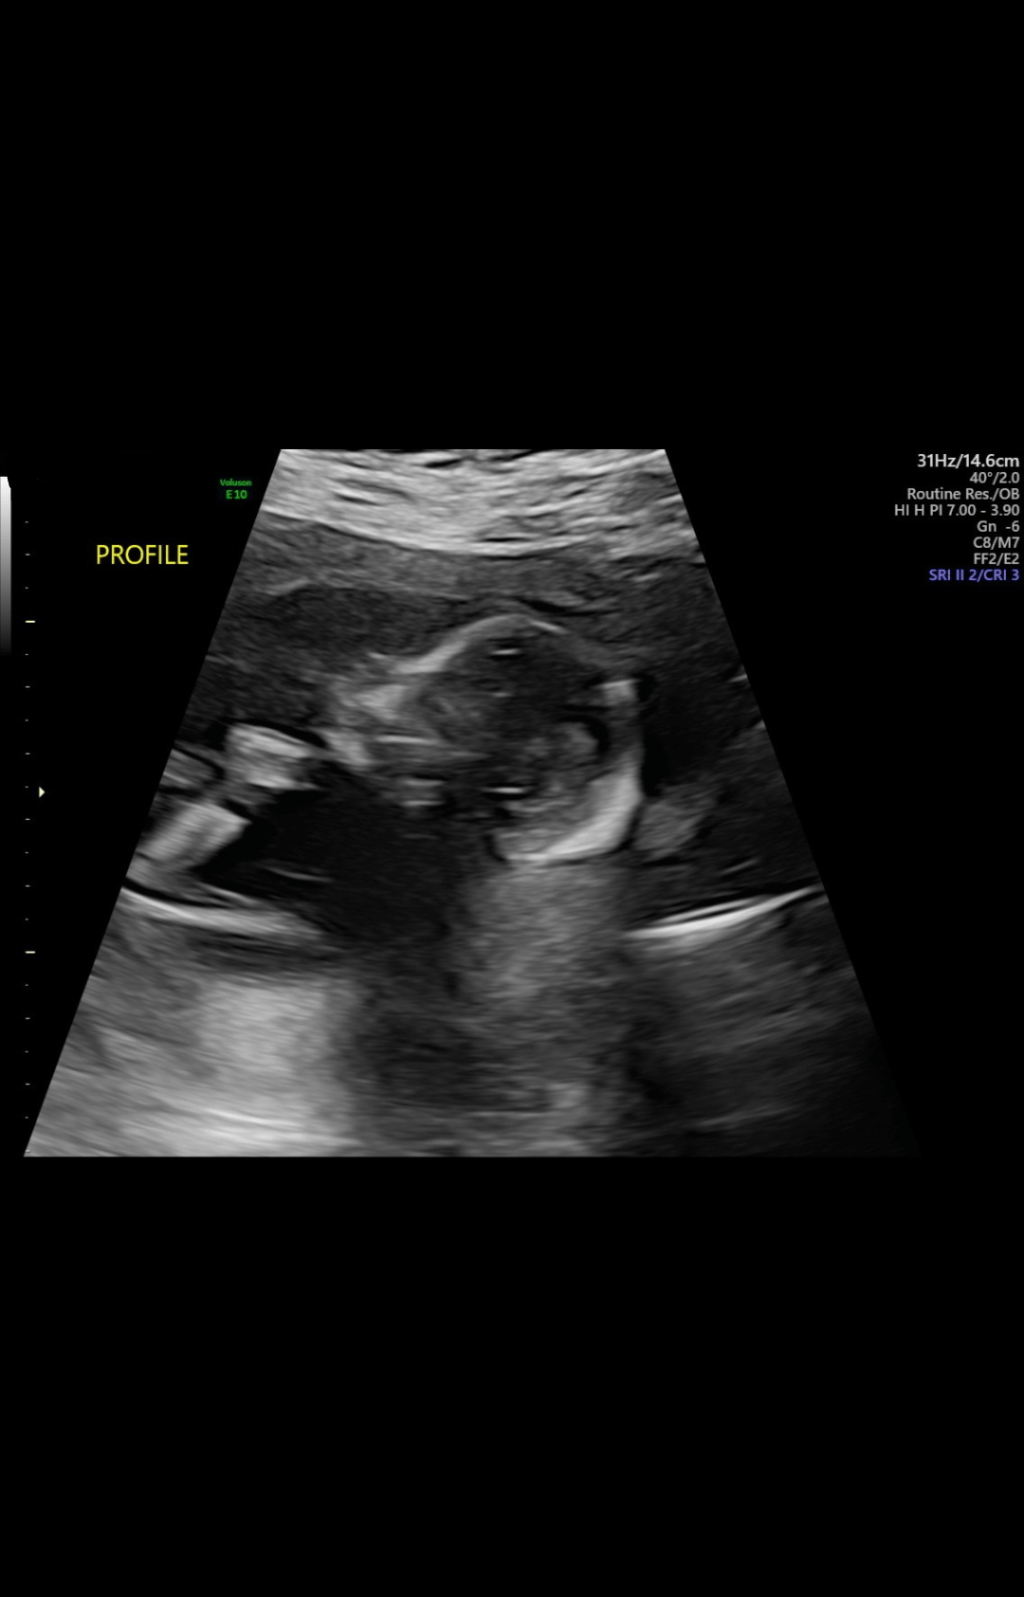

And now, here I am, pregnant again at 39. This time the journey was different from the beginning. It took multiple IUIs & a lot of waiting, hoping, & praying. Every single step has been layered with cautious hope, guarded excitement, & the fear of getting attached too soon.

People will ask me, “Aren’t you so excited?” And I truly am. But excitement doesn’t look the same this time around. Its quieter & more sacred. It’s mixed with nerves and flashbacks and little moments that remind me of what we lost. There are days that I feel confident & hopeful, and then there are days when I’m afraid to think too far ahead, afraid to make plans, & afraid to let myself imagine life with this baby in it just yet.

No one talks about how even the good parts, hearing the heartbeat, the ultrasounds, the kicks, can feel scary. With every milestone, there’s a “what if”. And so, I hold back. I haven’t bought any baby clothes, or any baby items at all, & I haven’t set up a nursery. Not because I’m not excited, but because I know how it feels to pack up the dreams you thought were coming true & put those things away. There’s a part of me that’s afraid to connect too deeply, it’s like a defense mechanism. Yet, there’s another part that desperately wants to believe that this time will be different. That this baby is coming home. That it’s okay to let myself feel joy again.